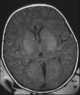

Hypoxic-ischemic encephalopathy

Cerebral hypoxia is a form of hypoxia (reduced supply of oxygen), specifically involving the brain; when the brain is completely deprived of oxygen, it is called cerebral anoxia. There are four categories of cerebral hypoxia; they are, in order of severity: diffuse cerebral hypoxia (DCH), focal cerebral ischemia, cerebral infarction, and global cerebral ischemia. [Source: Wikipedia ]